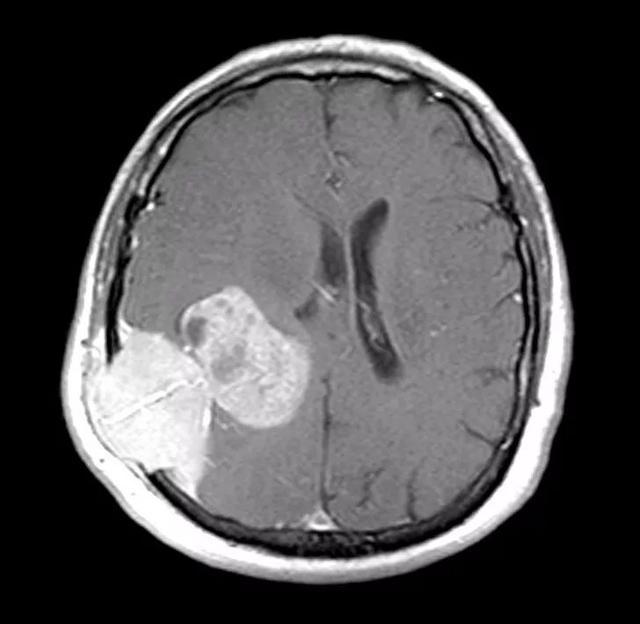

脑部肿瘤